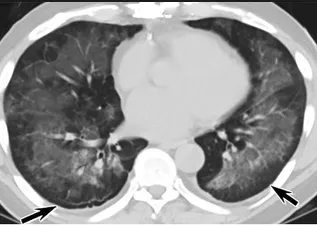

更值得注意的是,有之前应对过武汉新冠疫情的中国权威肺病专家,在查阅了60篇涉及美国“电子烟肺病”病例的研究论文,并对其中142位电子烟肺病患者的250张肺部影像图片、临床信息以及文献原文进行了仔细全面的研究后,发现这些病例中有16个更有可能是新冠肺炎的“疑诊患者”,有5个临床症状和治疗情况相对完整的患者,还被这些专家认定为了“中度可疑”。另外,这16个病例中有12个病例的发病时间,都在2020年以前。

新冠病毒是否来自美国?迄今为止最全面的线索来了

(这4张图,是专家怀疑被误诊为电子烟肺病的其中一个病例的肺片。专家表示,他们不是仅仅通过一张影片做判断的,而是通过这4张涵盖了这名病例肺部多天变化情况的影片进行的研判,认为该病例的病程进展跟新冠更为相似)